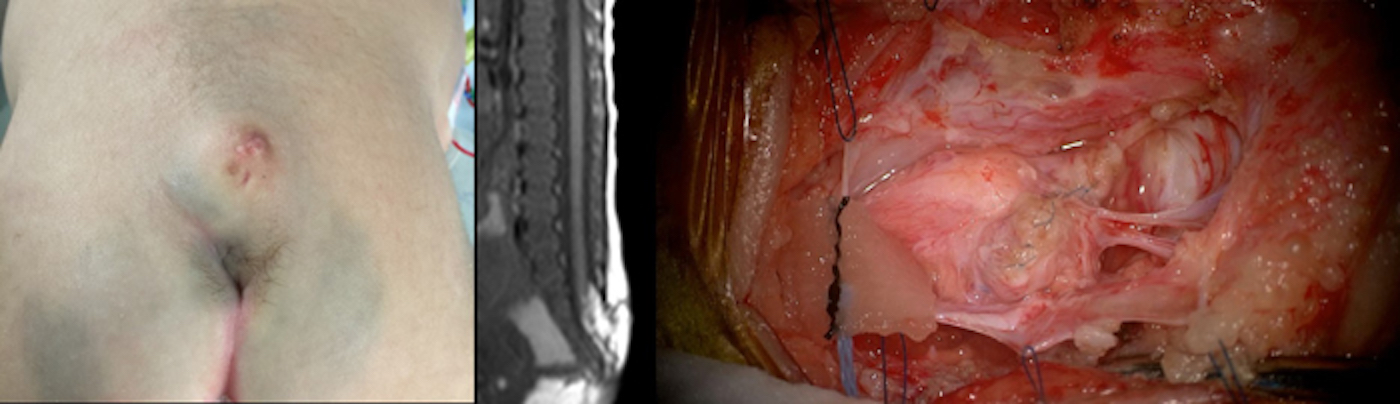

二分脊椎、くも膜のう胞などの先天性疾患、水頭症、脳腫瘍(神経皮膚症候群を含む)、もやもや病、脳動静脈奇形などの血管障害、外傷など広く取り扱っていおります。